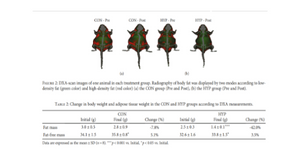

In this case, low-dose lithium supplementation was investigated and found to induce adipose tissue browning and sarco(endo)plasmic reticulum Ca2+ ATPase uncoupling in muscle.

Image Credit: Geromella MS, Ryan CR, Braun JL, Finch MS, Maddalena LA, Bagshaw O, Hockey BL, Moradi F, Fenech RK, Ryoo J, Marko DM, Dhaliwal R, Sweezey-Munroe J, Hamstra SI, Gardner G, Silvera S, Vandenboom R, Roy BD, Stuart JA, MacPherson REK, Fajardo VA. Low-dose lithium supplementation promotes adipose tissue browning and sarco(endo)plasmic reticulum Ca2+ ATPase uncoupling in muscle. J Biol Chem. 2022 Nov;298(11):102568. doi: 10.1016/j.jbc.2022.102568. Epub 2022 Oct 7. PMID: 36209826; PMCID: PMC9664358.